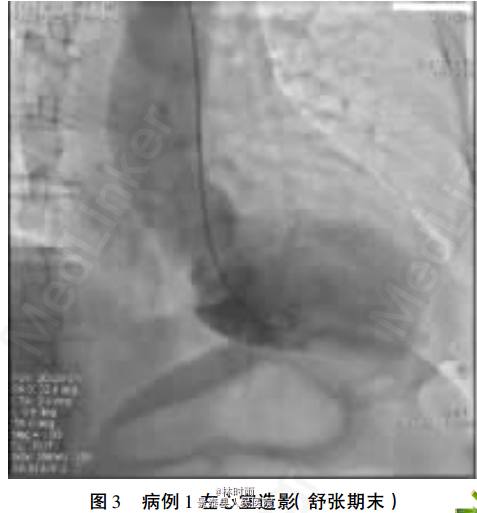

初步诊断——冠心病:急性下壁心肌梗死。(结合患者年龄等多种冠心病危险因素、临床症状及心电图改变,考虑患者冠心病、急性下壁心肌梗死可能)。 处理——患者入院至症状发作4h,故行急诊冠脉造影,结果显示冠脉未见明显狭窄病变,行左心室造影,提示典型心尖球囊样综合征改变(见图3-4)。 住院期间监测患者心肌酶学指标均轻度升高,且酶学峰值不符合心肌梗死特点,肌钙蛋白T(cTnT)于发病72h基本恢复正常水平。另予β阻滞剂治疗。 确定诊断——心尖球囊样综合征。

术后1周复查超声心动图显示左室整体室壁运动协调。心尖球囊样综合征大部分病人发病前有心理或躯体等相关应激因素,而后出现类似急性心肌梗死的临床表现,但冠脉造影无器质性狭窄病变。 符合一支以上冠脉供血区域的室壁运动障碍,因其左室造影收缩期的形态显示底部圆形、颈部细窄呈气球样,故称为心尖球囊样综合征,又称为Tako-Tsubo 综合征、 应激性心肌病及一过性左室功能不全综合征。 日本报道有1%-2%的临床表现与AMI相似的病人最后被确诊为本病,而绝经后女性所占比例较高。 本病预后相对良好,关于其诊断亦无统一标准,有学者总结归纳的诊断标准为: ①主要标准:可逆性左心室心尖部球囊样运动异常伴基底部过度收缩,心电图改变类似于AMI; ②次要标准:情绪等诱发,临床有胸痛、 胸闷等症状,伴有心肌酶学指标升高。本患者为绝经后女,发病前有明确的情绪应激诱因,发作时心电图均表现为下壁、 前壁及侧壁导联的T高尖、ST段抬高,继而多导联T波明显倒置,不符合单一冠脉供血区心肌梗死心电图导联改变;心肌酶谱的动态变化特点亦不同于AMI;1周内左心室心肌运动明显改善。 本研究病例心肌酶升高,但升高峰值相对心肌梗死峰值低,与超声心动图的大面积室壁运动障碍不相符,酶学升高曲线与心肌梗死不同,且 7天后仍未恢复正常,均符合心尖球囊样综合征临床特点。【转载自:《临床和实验医学杂志》2013年3月第12卷第5期,《心尖球囊样综合征2例报告》】